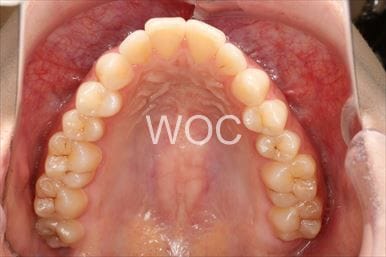

治療後1

- 年齢:20歳女性

- 主訴:出っ歯が気になる

- 基本矯正料金:120万円

- 治療期間:1年7ヶ月

- 抜歯部位:上顎両側第一小臼歯